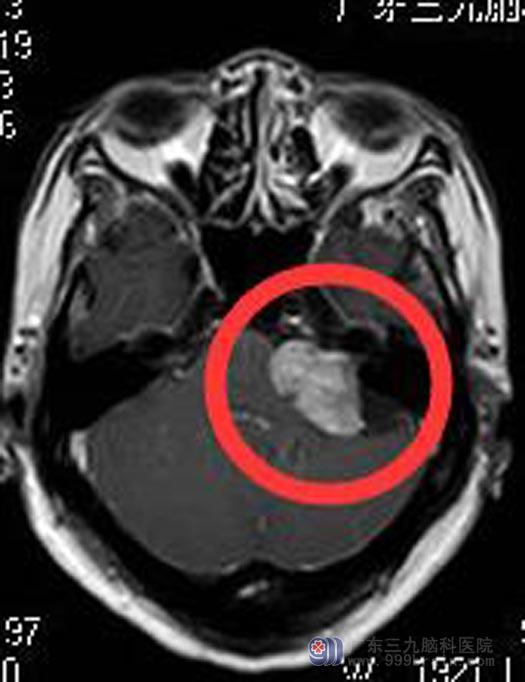

广东三九脑科医院进一步行头颅MR检查提示:左侧桥小脑角区占位性病变,大小约3.8cm×2.2cm×2.1cm,邻近左侧桥臂及脑干受压,四脑室受压变窄,考虑听神经瘤可能。

详细了解病情后,家属同意手术切除。综合神经外科鲁明主任主刀,在全麻下行左侧桥小脑角区听神经瘤切除术,术中显微镜下见肉红色肿瘤组织,包膜完整,被小脑前下动脉包绕,质中,血供丰富,全切肿瘤,面神经、听神经、后组颅神经保留完好。术后陈女士没有出现后组颅神经损害症状,已满意出院。术后病理回报:神经鞘瘤。